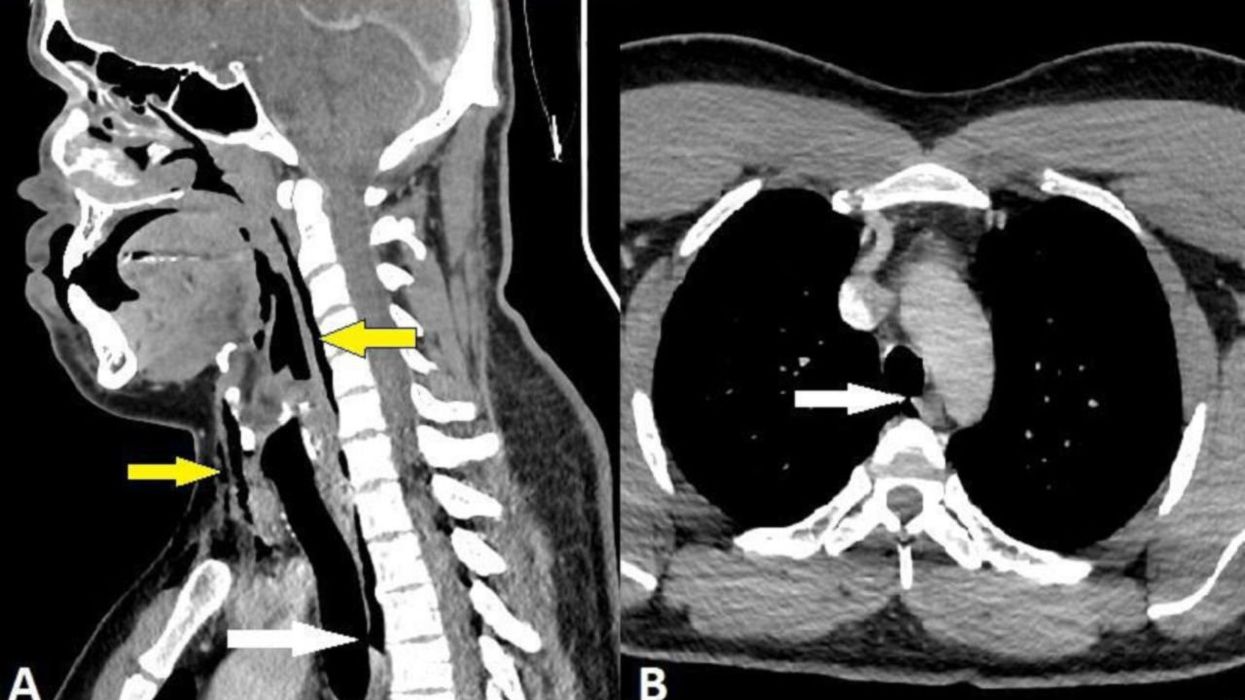

After an x-ray, it was discovered that the man had a condition called surgical emphysema, where air can get stuck under the deepest tissue in someone's body. The air had gotten trapped in the vertebrae in the man's neck as well as the space in between his chest and lungs.

Ultimately, it was determined by doctors that the man didn't need surgery and that the tear was caused by a "rapid build-up of pressure in the trachea while sneezing with a pinched nose and closed mouth."